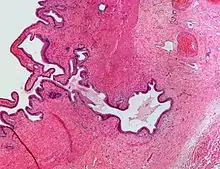

| Micrograph showing Rokitansky–Aschoff sinus. H&E stain. |

Rokitansky–Aschoff sinuses

Rokitansky–Aschoff sinuses are pseudodiverticula or pockets in the wall of the gallbladder. They may be microscopic or macroscopic. Histologically, they are outpouchings of gallbladder mucosa into the gallbladder muscle layer and subserosal tissue as a result of hyperplasia and herniation of epithelial cells through the fibromuscular layer of the gallbladder wall.[4]

Rokitansky–Aschoff sinuses are not of themselves considered abnormal but they can be associated with cholecystitis.[5]

They form as a result of increased pressure in the gallbladder and recurrent damage to the wall of the gallbladder.[6]